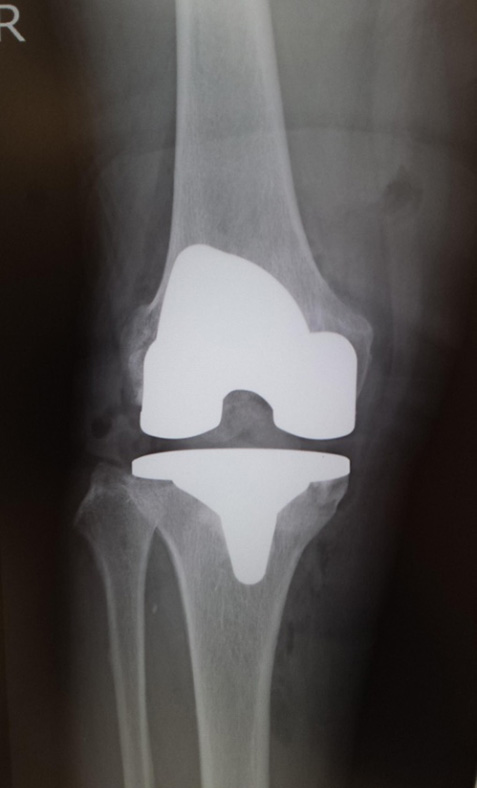

当院でおこなった人工膝関節全置換術(TKA)

手術前

手術直後